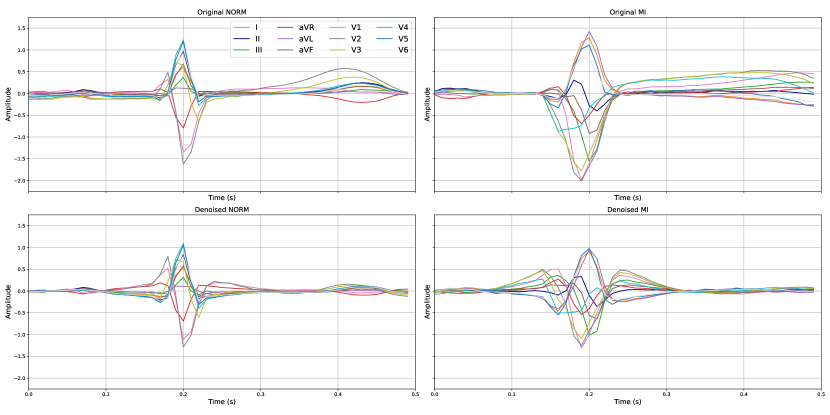

The effect of denoising on one beat is demonstrated for two random samples in Figure C.3. Moreover, in Figure C.4, we can also observe how the signal in each lead changes discretely for the samples.